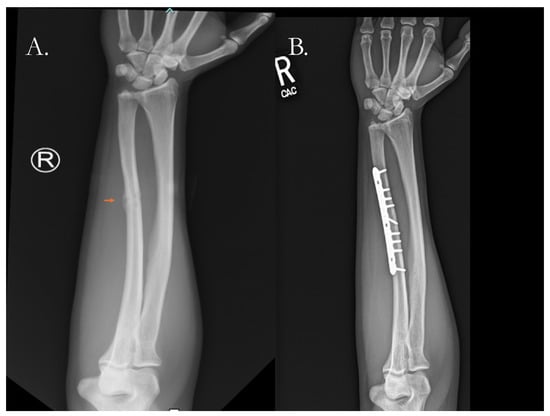

- Mazzotta, A.; Stagni, C.; Rocchi, M.; Rani, N.; Del Piccolo, N.; Filardo, G.; Dallari, D. Bone Marrow Aspirate Concentrate/Platelet-Rich Fibrin Augmentation Accelerates Healing of Aseptic Upper Limb Nonunions. J. Orthop. Traumatol. 2021, 22, 21. [Google Scholar] [CrossRef]

- Ma, X.-Y.; Liu, B.; Yu, H.-L.; Zhang, X.; Xiang, L.-B.; Zhou, D.-P. Induced Membrane Technique for the Treatment of Infected Forearm Nonunion: A Retrospective Study. J. Hand Surg. 2022, 47, 583.e1–583.e9. [Google Scholar] [CrossRef]